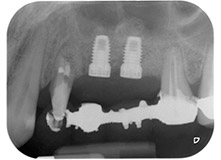

Дефицитът на кост около имплантите, от мезиален аспект на зъб 27 и около букалния корен на зъб 24, е запълнен с ксеногенни костозаместващи частици и покрит с абсорбираща колагенова мембрана (Bio-Gide, Geistlich Biomaterials) за GBR аугментация (Фиг. 13 и 14).

Накрая, след периостален разрез, мястото е пасивно зашито с коронарно напреднало ламбо, използвайки 5-0 абсорбиращ конец (Фиг. 15). Следоперативната рентгенова снимка показва, че и двата импланта са в правилна вертикална позиция (Фиг. 16).